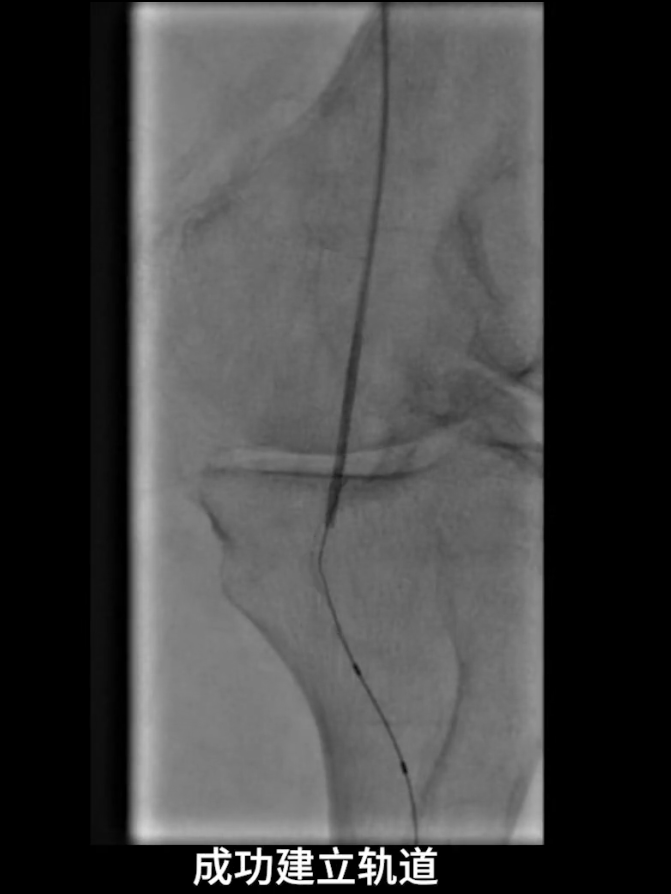

首先尝试顺行通过股浅动脉闭塞段,导丝进入内膜下,开通失败;遂改为逆穿策略,以支撑导管配合V18导丝逆行通过股浅动脉闭塞段,最终与近端股浅动脉真腔成功对接,建立安全操作轨道。

逆穿技术应用:改为逆穿胫后动脉远端,支撑导管配合V18导丝经交通支逆行进入腓动脉远端,逐步推送导丝导管通过胫腓干闭塞段,直至腘动脉近端真腔,与近端导管完成对接,建立膝下流出道操作轨道。